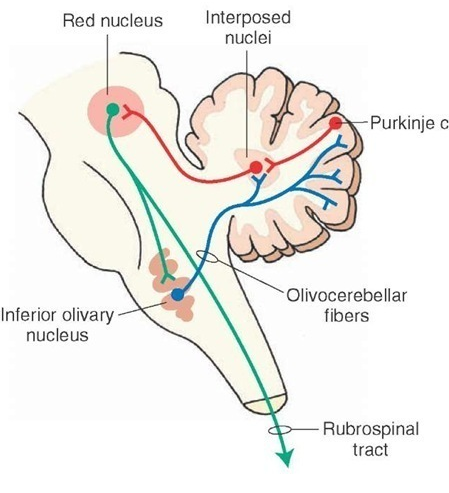

what is the course of the cortico-rubro-olivary circuit)

cortex –> red nucleus —> inferior olive —> cerebellum